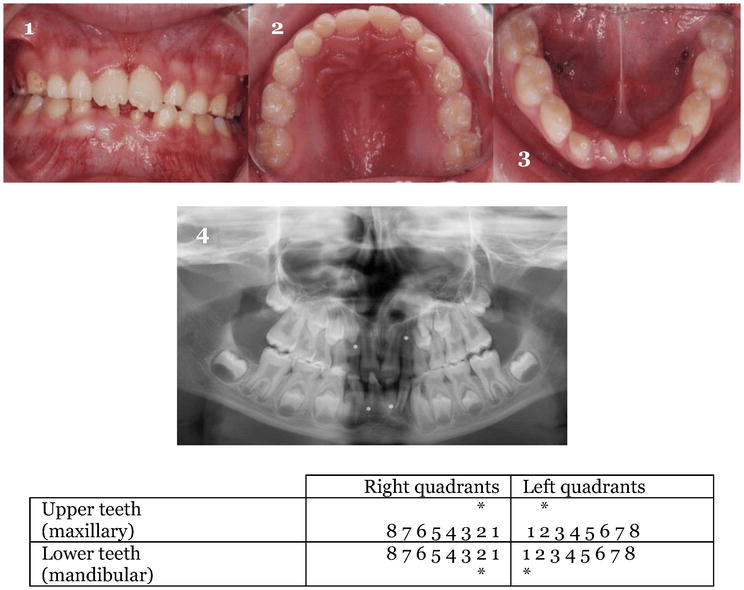

Tooth agenesis in a down syndrome male patient, aged 8 years old. (13 Incisor Agenesis Meaning Maxillary lateral incisor agenesis poses a complex challenge for dentists due to its impact on smile aesthetics and occlusal. Tooth agenesis occurs when there is a developmental absence of one or more of the ‘normal’ complement of 20 teeth in the primary. Treating maxillary lateral incisor agenesis requires the joint work of a multidisciplinary team that, after evaluating all. To. Incisor Agenesis Meaning.

Tooth agenesis in a down syndrome male patient, aged 8 years old. (13 Incisor Agenesis Meaning Maxillary lateral incisor agenesis poses a complex challenge for dentists due to its impact on smile aesthetics and occlusal. The agenesis of maxillary lateral incisors is a common developmental anomaly and represents a clinical problem impairing dental esthetics and. Tooth agenesis occurs when there is a developmental absence of one or more of the ‘normal’ complement of 20 teeth in. Incisor Agenesis Meaning.